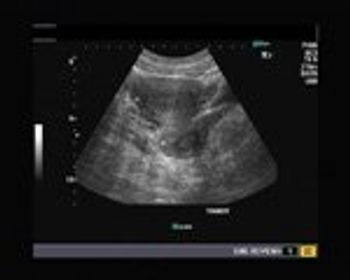

This is an ultrasound scan of the pelvis in 35 year old female patient.

Using only this image, describe what phase of the menstrual cycle this patient is in.